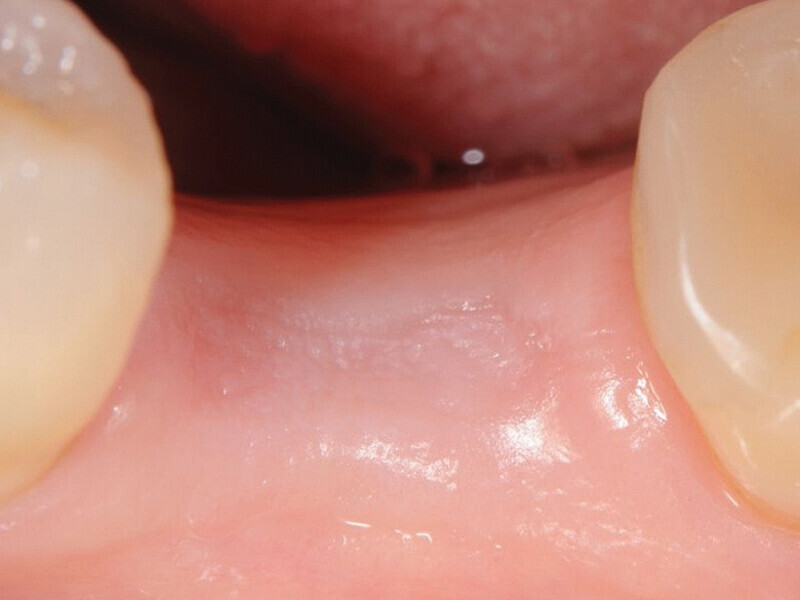

Fig. 7: Healing period with healing cap ZERAMEX XT. (Photo: Jens Tartsch, DMD)